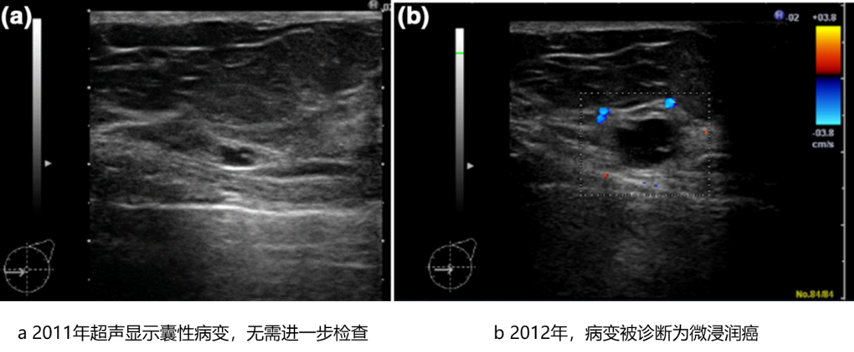

6,512例患者被诊断为囊性病变,基本上是2类和良性,但有1例(0.015%)恶性,如下图所示。超声显示为囊性,无需进一步检查,但患者一年后进行机会性筛查时,发现一个内部有轻微回声的囊内肿瘤,进一步检查诊断为微浸润癌(0.5 mm)。

图片44.png